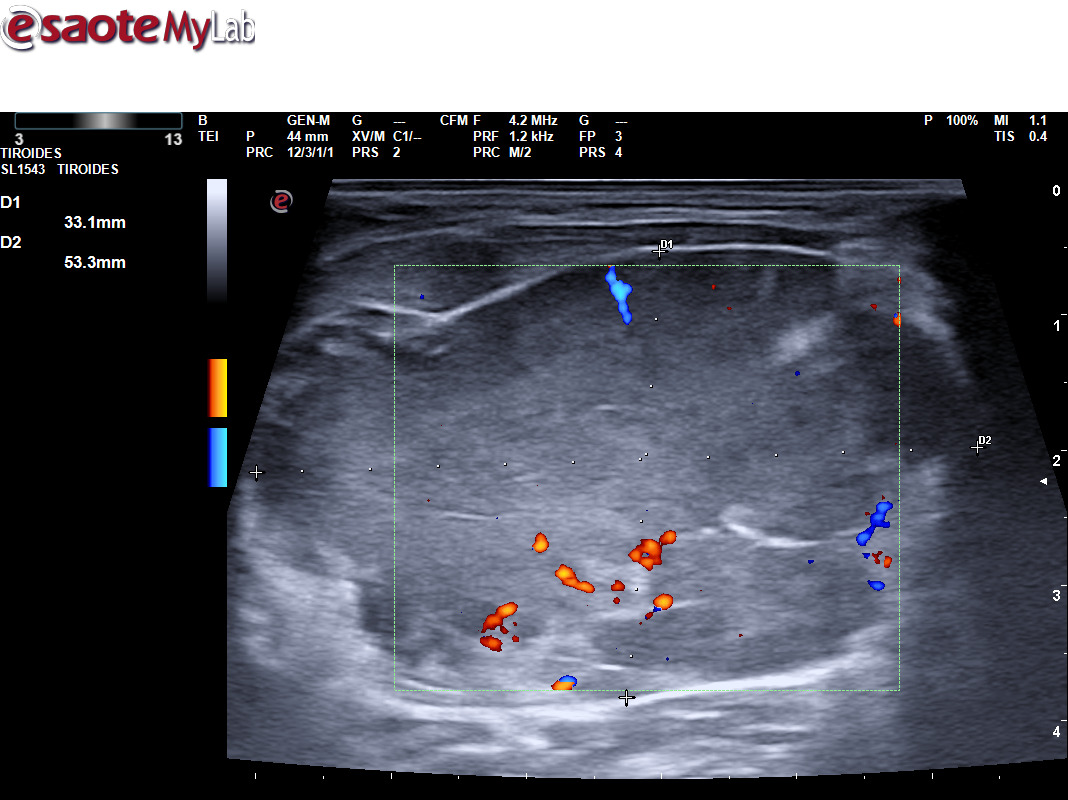

A través de distintos casos clínicos queremos valorar la importancia de la ecografía clínica en pacientes que consultan por la aparición de una masa cervical. Tras valorar a varios pacientes que han consultado por una masa cervical, hemos realizado una sesión clínica formativa sobre el aprendizaje de la ecografía cervical. Durante este periodo hemos podido diagnosticar diferentes patologías utilizando ecografía clínica y apoyándonos en otras pruebas complementarias, como un tumor de Merkel, un tumor de Warthin, una mononucleosis infecciosa, inflamación de un ganglio linfático por infección, un adenoma pleomorfo en glándula submandibular, malformación vascular, microlitiasis parotídeas, tuberculosis y un mieloma múltiple.

La ecografía ayuda a determinar las características de la masa, como su tamaño, forma y consistencia, lo que puede ayudarnos en la sospecha de patología maligna.

Permite distinguir entre diferentes tipos de tejidos, como quistes, ganglios linfáticos inflamados o tumores, lo que es crucial para un diagnóstico adecuado.